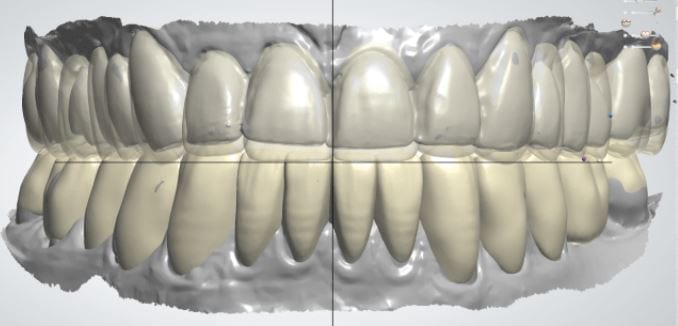

The digital models were then imported into a third party software where a library of tooth morphologies are available for the clinician to choose from.

Once the appropriate library is chosen, the digital wax ups are performed. In the subsequent photos you can see the transparent overlay of the wax-ups to the original position of the existing dentition

Once the case is designed to the ideal vertical dimension then multiple shells can be fabricated for treatment. The wax up model can be uniformly reduced by .5mmm’s circumferentially and a temporary shell can be designed. Once the teeth are prepared, these shells can be relined and seated onto the preps.